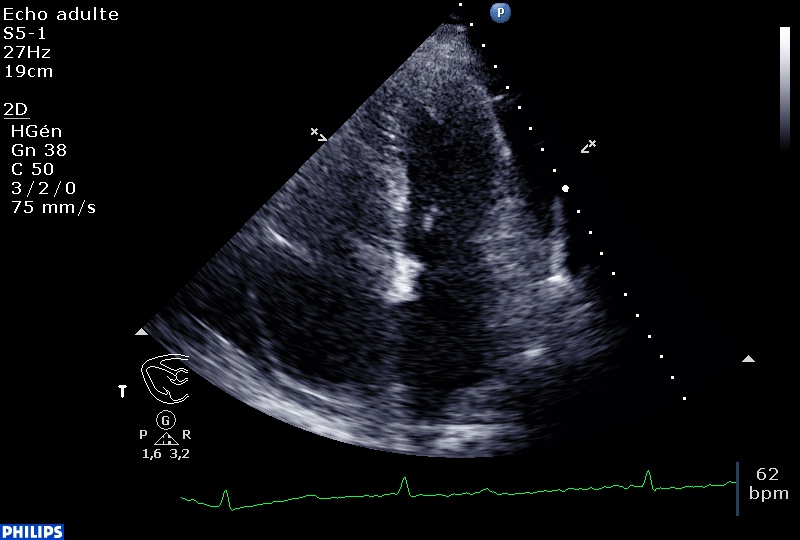

-Épanchement perciardique circonférentiel, non compressif, de 10-12 mm au maximum, par ailleurs déjà noté sur une échographie réalisée 6 mois auparavant pour exploration d’une cytolyse.

-Arguments pour des pressions de remplissage gauches élevées avec onde E véloce, un E/Ea >15, aspect restrictif (mais composante atriale faible post CEE) et grande onde D dans le flux de la veine pulmonaire supérieure droite.

-En TM en sous costal, à droite et à gauche de l’écran, on peut voir la courbure septale s’inverser avec un VD qui refoule le septum inter ventriculaire vers les cavités gauches.